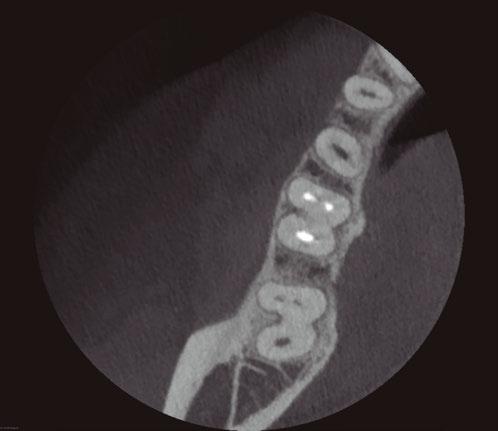

tissue lesions, or root resorption radiographically. After 2 years of GWS, cone beam computed tomography (CBCT) images show intact lamina dura and growth of trabecular bone in Figure 1D.

A postoperative radiograph is presented in Figure 1C. At the 2-year recall, the patient was asymptomatic. Upon clinical and radiographic examination, there was no painful response to percussion or palpation, no presence of mobility, fractures, soft

A 75-year-old female patient with a noncontributory medical history was referred with a chief complaint of dull pain in the lower right quadrant for 1 month, worsened by pressing on the gum. The patient reported a history of crown preparations of teeth Nos. 30 and 31, 1 week prior. Gingival swelling for several days had partially subsided since starting antibiotic therapy. Clinical examination of the right first maxillary molar (No. 30) revealed negative sensitivity to percussion and a mild pain response to palpation. There was a vestibular swelling over the mesial root of tooth No. 30. Vitality testing elicited a negative response. Radiographic examination revealed a large periapical lesion on the mesial root of tooth No. 30 (Figure 2A). The patient’s history of symptoms and the clinical examination indicated a diagnosis of

Upon completion of endodontic therapy with the GWS, at the 6-month recall, the tooth was asymptomatic (Figure 2C). The CBCT was taken, and images showed complete healing of the apical bone (Figure 2D).

Figure 2D: CBCT images with no evidence of periapical lesion of Case 2